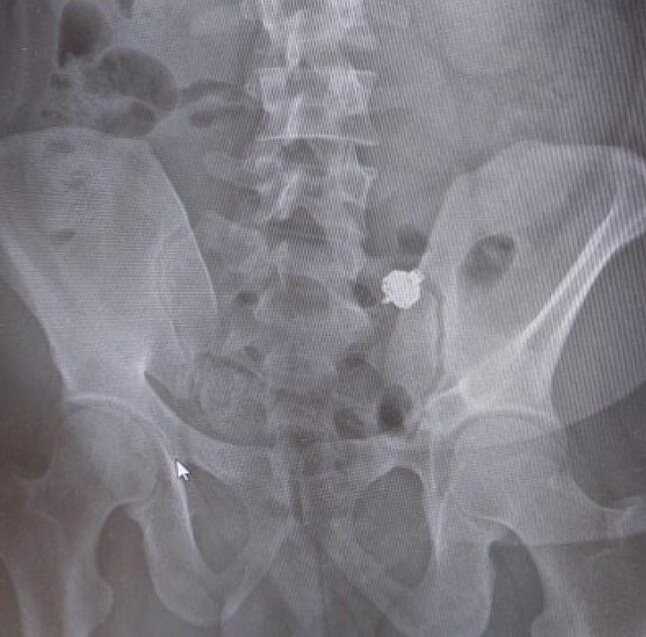

Ao perceber que havia sido descoberto, o homem não teve dúvidas: engoliu o fone de ouvido, na esperança de se livrar das evidências. Ele não contava, porém, que seria levado ao hospital para fazer um raio-X.

O exame mostrou que o fone de ouvido ainda estava em seu estômago, e que ele não conseguiria digeri-lo. O homem, que não teve seu nome divulgado, terá que responder por fraude e falsidade ideológica.